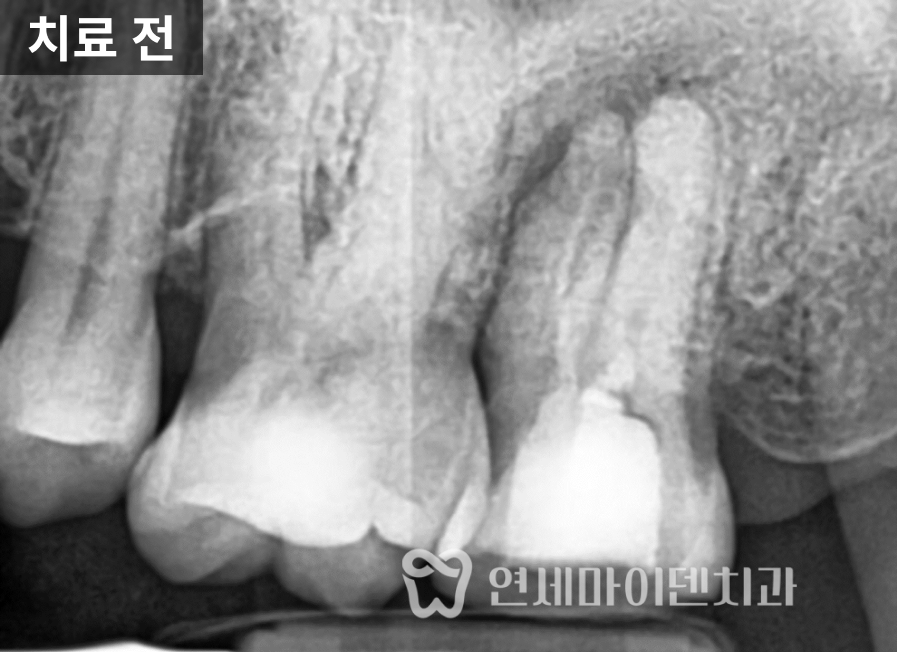

X-ray를 확인해보면,

반대편 어금니는 뼈 상태가 비교적 건강한 반면문제 부위는 치조골 높이가

절반 가까이 무너진 상태였습니다이 때문에 이전 병원에서는

“앞 치아도 곧 못 쓴다”며

두 개 모두 임플란트를 권유받았던 상황이었습니다.

하지만, 앞쪽 어금니의 경우

뿌리 앞쪽 뼈는 비교적 단단하게 남아 있었고

염증 범위도 제한적이어서

충분히 보존 가능성이 있는 상태였습니다.즉,

무조건 두 개를 다 뽑아야 할 상황은 아니었습니다.치료 방향: “하나는 살리고, 하나는 심자”